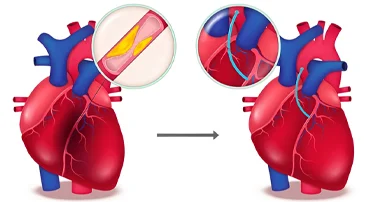

Heart Bypass Surgery Cost in Jaipur, India: A Complete Guide

Heart bypass surgery is a type of surgery that creates a new path for blood to flow when your heart’s arteries are blocked. Cardiologists usually take a healthy blood vessel from your chest or leg and connect it around the blocked artery.

A Complete Guide to Heart Bypass Surgery: Why It’s Done, How It Works & What to Expect

Heart bypass surgery, or coronary artery bypass grafting (CABG), is a life-saving surgery that is done to enhance the flow of blood to the heart when the coronary arteries are blocked or narrowed very much. Such a condition, or coronary artery disease (CAD), may result in chest pain (angina), shortness of breath, and a higher risk of heart attacks.

Heart Bypass Surgery: Purpose, Procedure, Risks And Recovery

Heart bypass surgery, also called CABG, is a critical surgical procedure used to ensure adequate blood flow to the heart when the coronary arteries have blockages or are narrowed with coronary artery disease (CAD). Blockages in the coronary arteries reduce the oxygen supply to the heart. This can result in chest pain and shortness of breath, and may even lead to heart attacks, which can be fatal. This surgical procedure is often recommended when lifestyle modification, drugs, or other minimally invasive treatments do not respond to the condition.